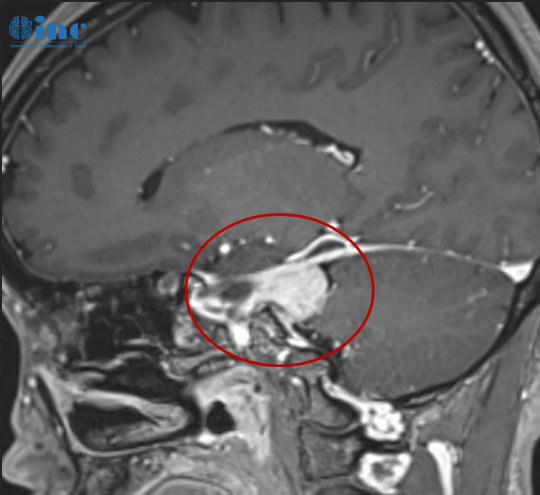

首刀、伽马刀后脑膜瘤多发恶化,INC巴教授Simpson 1级全切术,4年没有复发

一次手术只实施了部分切除。

二年病变复发,他接受了伽玛刀治疗,

三年病变竟然恶化成了多发性脑膜瘤。

经过多方寻医,赵先生的女儿联系到INC神经外科专家巴特朗菲教授,

教授看过赵先生的病理资料后表示,虽然二次手术风险大,但仍可实现全切肿瘤。

在术中神经电生理检测护航下,巴教授顺利全切肿瘤,术中无神经损伤,预后无并发症。

巴教授表示,脑膜瘤及其残余已得到全切,后期再做一些康复治疗和定期复查,10年生存率可达80%。

现在,赵先生已经康复4年,未再出现病变复发,生活恢复如常。